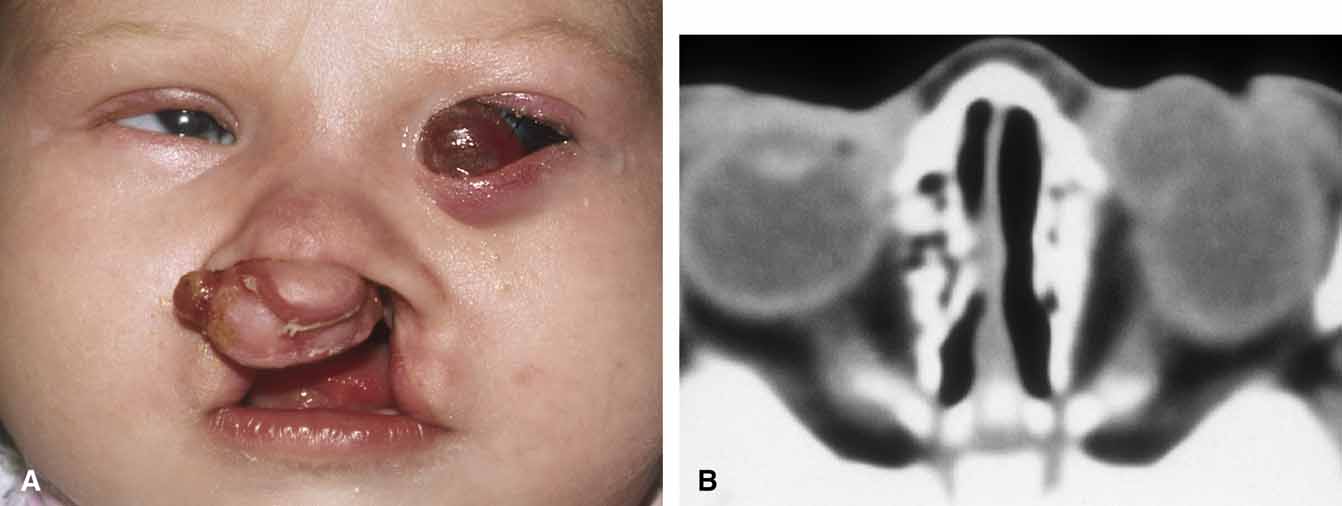

Because of the variable presentation of dermoid cysts, Shields et al.,5 have suggested a classification of orbital dermoid cysts by their association (or lack of association) with suture lines of the skull and assist the clinician in appropriate management. Cysts are classified as juxtasutural, sutural, or soft-tissue dermoid cysts. Those cysts adjacent to the bony suture line but not firmly attached are juxtasutural. A sutural dermoid cyst is firmly attached to bony sutures causing bone erosion, tunnels or an hourglass configuration. Soft tissue dermoid cysts may be strictly confined to soft tissues without any connection to a bone structure. Intradiploic epidermoid cysts are distinctly uncommon and were not included in Shields' classification (Fig. 3).